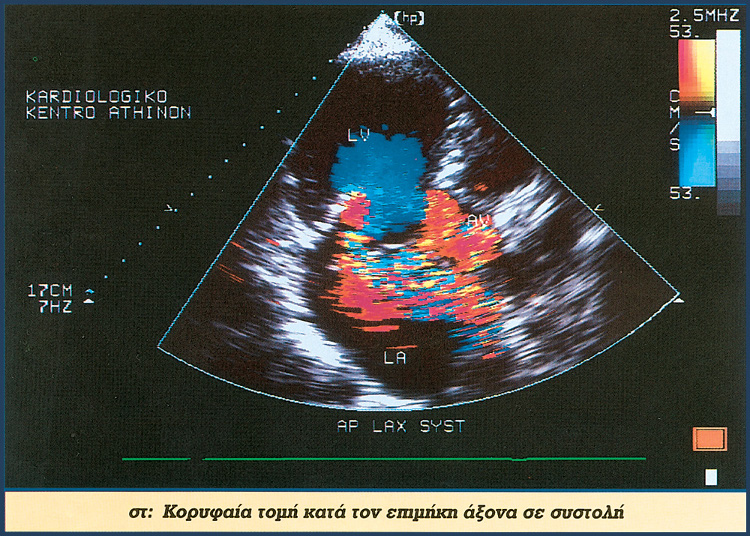

Υπερηχοκαρδιογραφική μελέτη φυσιολογικής καρδιάς με νεώτερες τεχνικές

HXOIXRWMA TEYXOS2 1

HXOIXRWMA TEYXOS2 2

HXOIXRWMA TEYXOS2 3

HXOIXRWMA TEYXOS2 4

HXOIXRWMA TEYXOS2 E

HXOIXRWMA TEYXOS2 ST